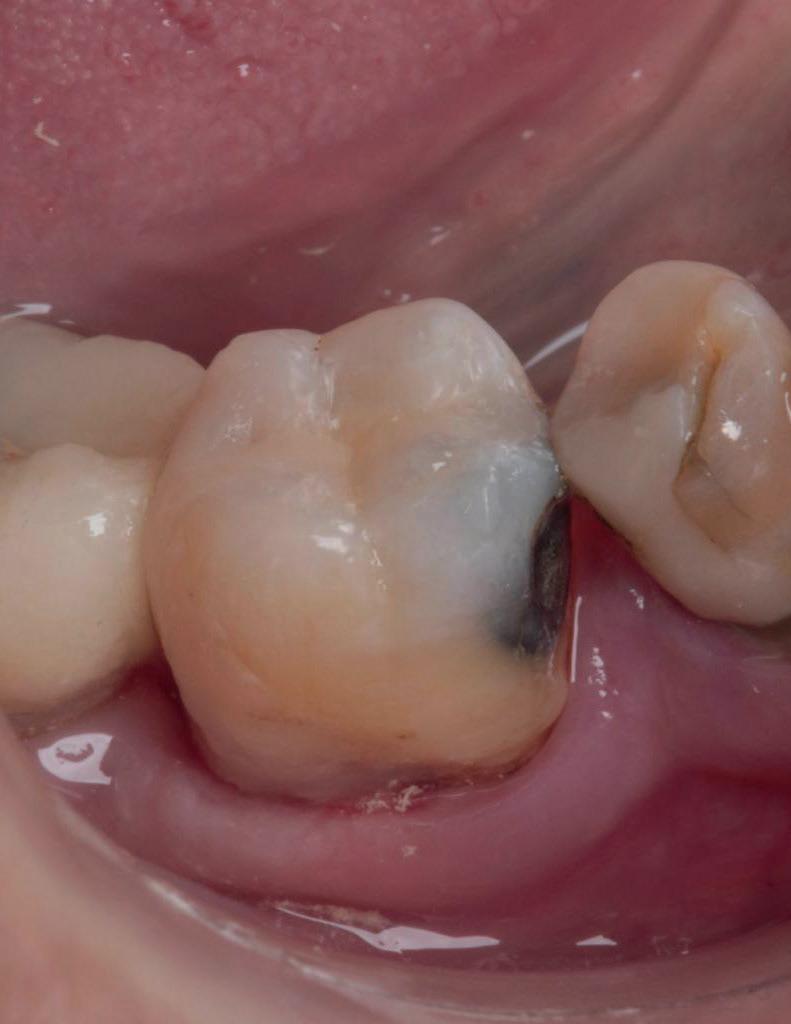

De casus

De verwijzend tandarts is bezig om een wortelkanaalbehandeling uit te voeren in gebitselement 27. Er zijn vier kanalen gevonden, maar helaas breekt er in het mesiobuccale kanaal (MB 1) een WaveOne vijltje af, maat geel (foto 2). Het lukt de tandarts niet om

2. Het afgebroken instrument op de foto van de verwijzend tandarts.

3. De opening is vrij klein gekozen. In rood is de ideale opening aangegeven, de tandarts had veel meer restauratiemateriaal mogen wegnemen.

het vijltje te verwijderen. De patiënte wordt verwezen voor het afmaken van de wortelkanaalbehandeling.

Als ik de patiënte zie, valt me op dat de opening die de tandarts gemaakt heeft, nogal klein is (foto 3). Eigenlijk is daar niet zoveel reden toe; als ik een ideale opening inteken (in rood), dan loopt een groot deel door restauratiemateriaal. Overwogen kan worden om de aanwezige mesiale box met restauratiemateriaal weg te halen als dat het zicht op de pulpakamer vergroot – ik verwijs naar de tip hierboven (wees bij het openen niet spaarzaam met het wegnemen van aanwezig restauratiemateriaal).